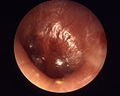

Chronic suppurative otitis media

Chronic suppurative otitis media involves a perforation (hole) in the eardrum and active bacterial infection within the middle ear space for several weeks or more. There may be enough pus that it drains to the outside of the ear (otorrhea), or the purulence may be minimal enough to only be seen on examination using a binocular microscope. This disease is much more common in persons with poor Eustachian tube function. Hearing impairment often accompanies this disease.